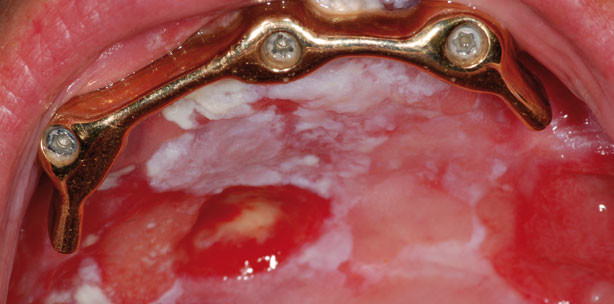

Mit der zunehmenden Zahl an dentalen Implantationen steigt auch die Prävalenz der periimplantären Entzündungen. Dr. Phillip Wallowy erläutert...

Mit der zunehmenden Zahl an dentalen Implantationen steigt auch die Prävalenz der periimplantären...